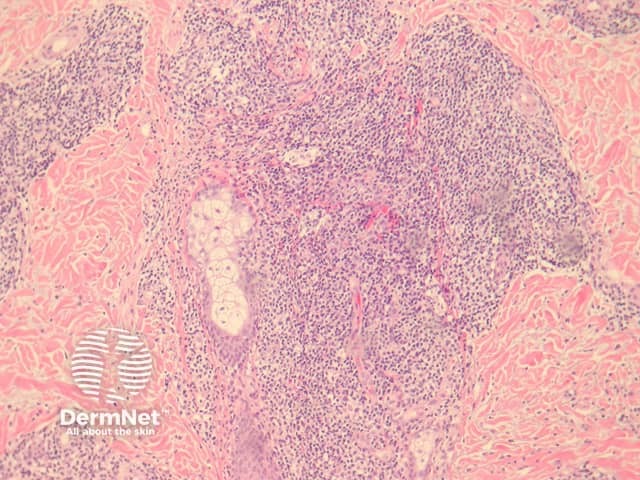

In DLE, sections reveal the dermis contains a perivascular and periadnexal lymphohistiocytic infiltrate under an interface dermatitis (figure 1). The epidermal interface activity shows degeneration of the basal layer, apoptotic keratinocytes and a marked thickening of the basement membrane (figures 2, 3). In well-established lesions, there may be marked follicular plugging (figure 4) and sometimes an epidermal reaction which may mimic a squamous cell carcinoma (verrucous lupus erythematosus). There is a characteristic lymphohistiocytic infiltrate surrounding appendages and vessels (figure 5). Deposition of dermal mucin may be impressive (figure 6).

Figure 1